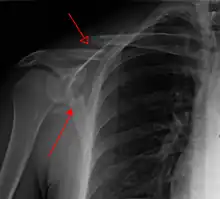

Most fractures of the scapula can be seen on a chest X-ray; however, they may be missed during examination of the film.[1] Serious associated injuries may distract from the scapular injury,[4] and diagnosis is often delayed.[3] Computed tomography may also be used.[1] Scapular fractures can be detected in the standard chest and shoulder radiographs that are given to patients who have had significant physical trauma, but much of the scapula is hidden by the ribs on standard chest X-rays.[4] Therefore, if scapular injury is suspected, more specific images of the scapular area can be taken.[4]